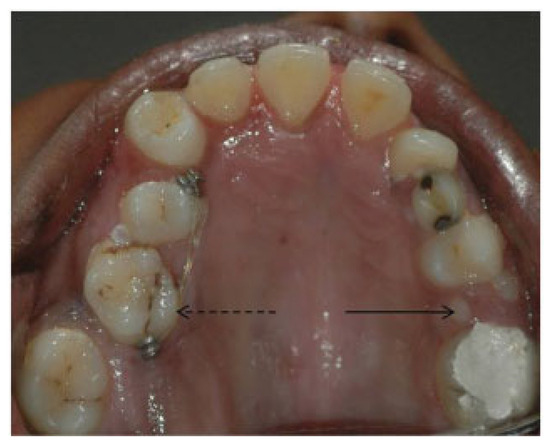

- Incomplete Tessier 7 soft tissue facial cleft and a complete skeletal Tessier 7 cleft on the right side

- Incomplete Tessier 5 skeletal and soft tissue Tessier 6 facial cleft on the left side